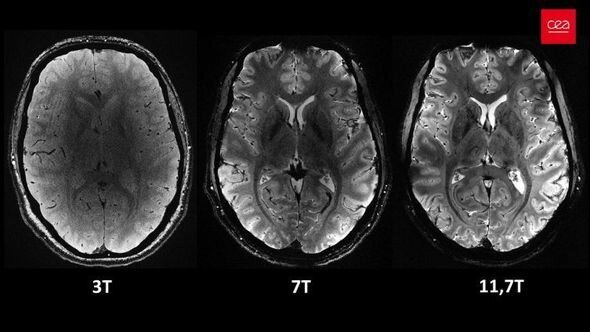

İnsan beyninin ən aydın görüntüsü dərc olunub - VİDEOElm adamları insan beyninin ən aydın görüntüsünü dərc ediblər. Şəkli dünyanın ən güclü maqnit rezonans tomoqrafiya (MRT) cihazı ilə əldə etmək mümkün olub.

Bildirilib ki, "Iseult" adlı MRT cihazı ilə çəkilən şəkil 20 ildən çox davam edən araşdırma nəticəsində əldə olunub.

Araşdırmalar çərçivəsində MRT cihazının son bir neçə ayda təxminən 20 sağlam könüllü üzərində sınaqdan keçirildiyi və ən aydın beyin görüntüsünün təxminən dörd dəqiqə ərzində əldə edildiyi ifadə edilib.

Açıqlamada qeyd olunub ki, 11,7 Tesla maqnit gücünə malik "Iseult" cihazı ilə qısa müddətdə çəkilən görüntüləri xəstəxanalarda istifadə edilən cihazlarla əldə etmək saatlar çəkə bilər.